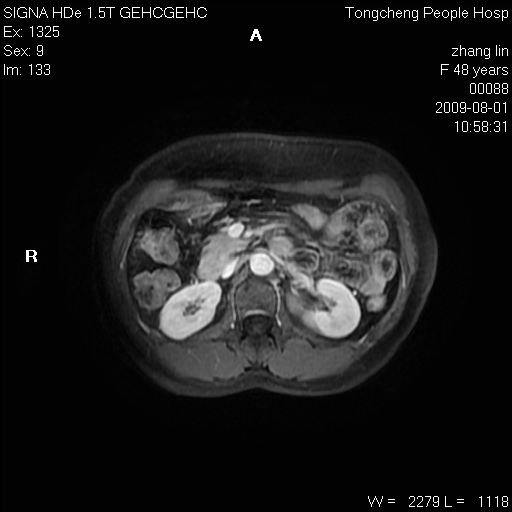

女,48岁。健康体检,彩超发现右肾占位性病变。平素健康。

临床诊断:右肾占位性病变,性质待定(囊肿?肿瘤?)。

上中腹部mr平扫+增强扫描,图像如下:

右肾上极见一类圆形病灶,t1wi呈等信号t2wi呈等高混杂信号,三期增强无强化,边界清---考虑囊肿出血。

同反相位均表现为等信号,病变无强化,考虑含蛋白的囊肿可能,弥散加权相或许有些帮助,

肝囊肿

慢性胆囊炎